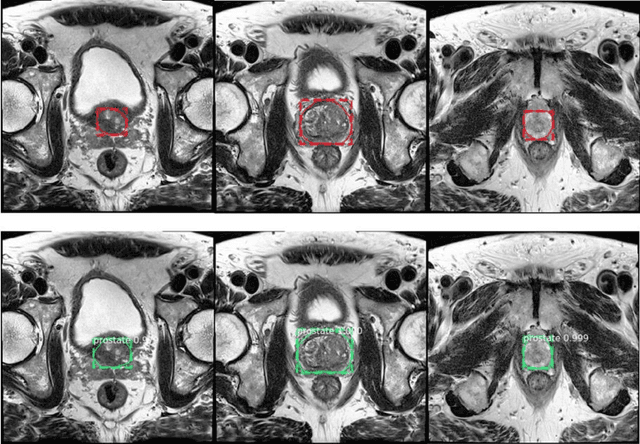

Abstract:Prostate cancer (PCa) is the most common cancer in men in the United States. Multiparametic magnetic resonance imaging (mp-MRI) has been explored by many researchers to targeted prostate biopsies and radiation therapy. However, assessment on mp-MRI can be subjective, development of computer-aided diagnosis systems to automatically delineate the prostate gland and the intraprostratic lesions (ILs) becomes important to facilitate with radiologists in clinical practice. In this paper, we first study the implementation of the Mask-RCNN model to segment the prostate and ILs. We trained and evaluated models on 120 patients from two different cohorts of patients. We also used 2D U-Net and 3D U-Net as benchmarks to segment the prostate and compared the model's performance. The contour variability of ILs using the algorithm was also benchmarked against the interobserver variability between two different radiation oncologists on 19 patients. Our results indicate that the Mask-RCNN model is able to reach state-of-art performance in the prostate segmentation and outperforms several competitive baselines in ILs segmentation.